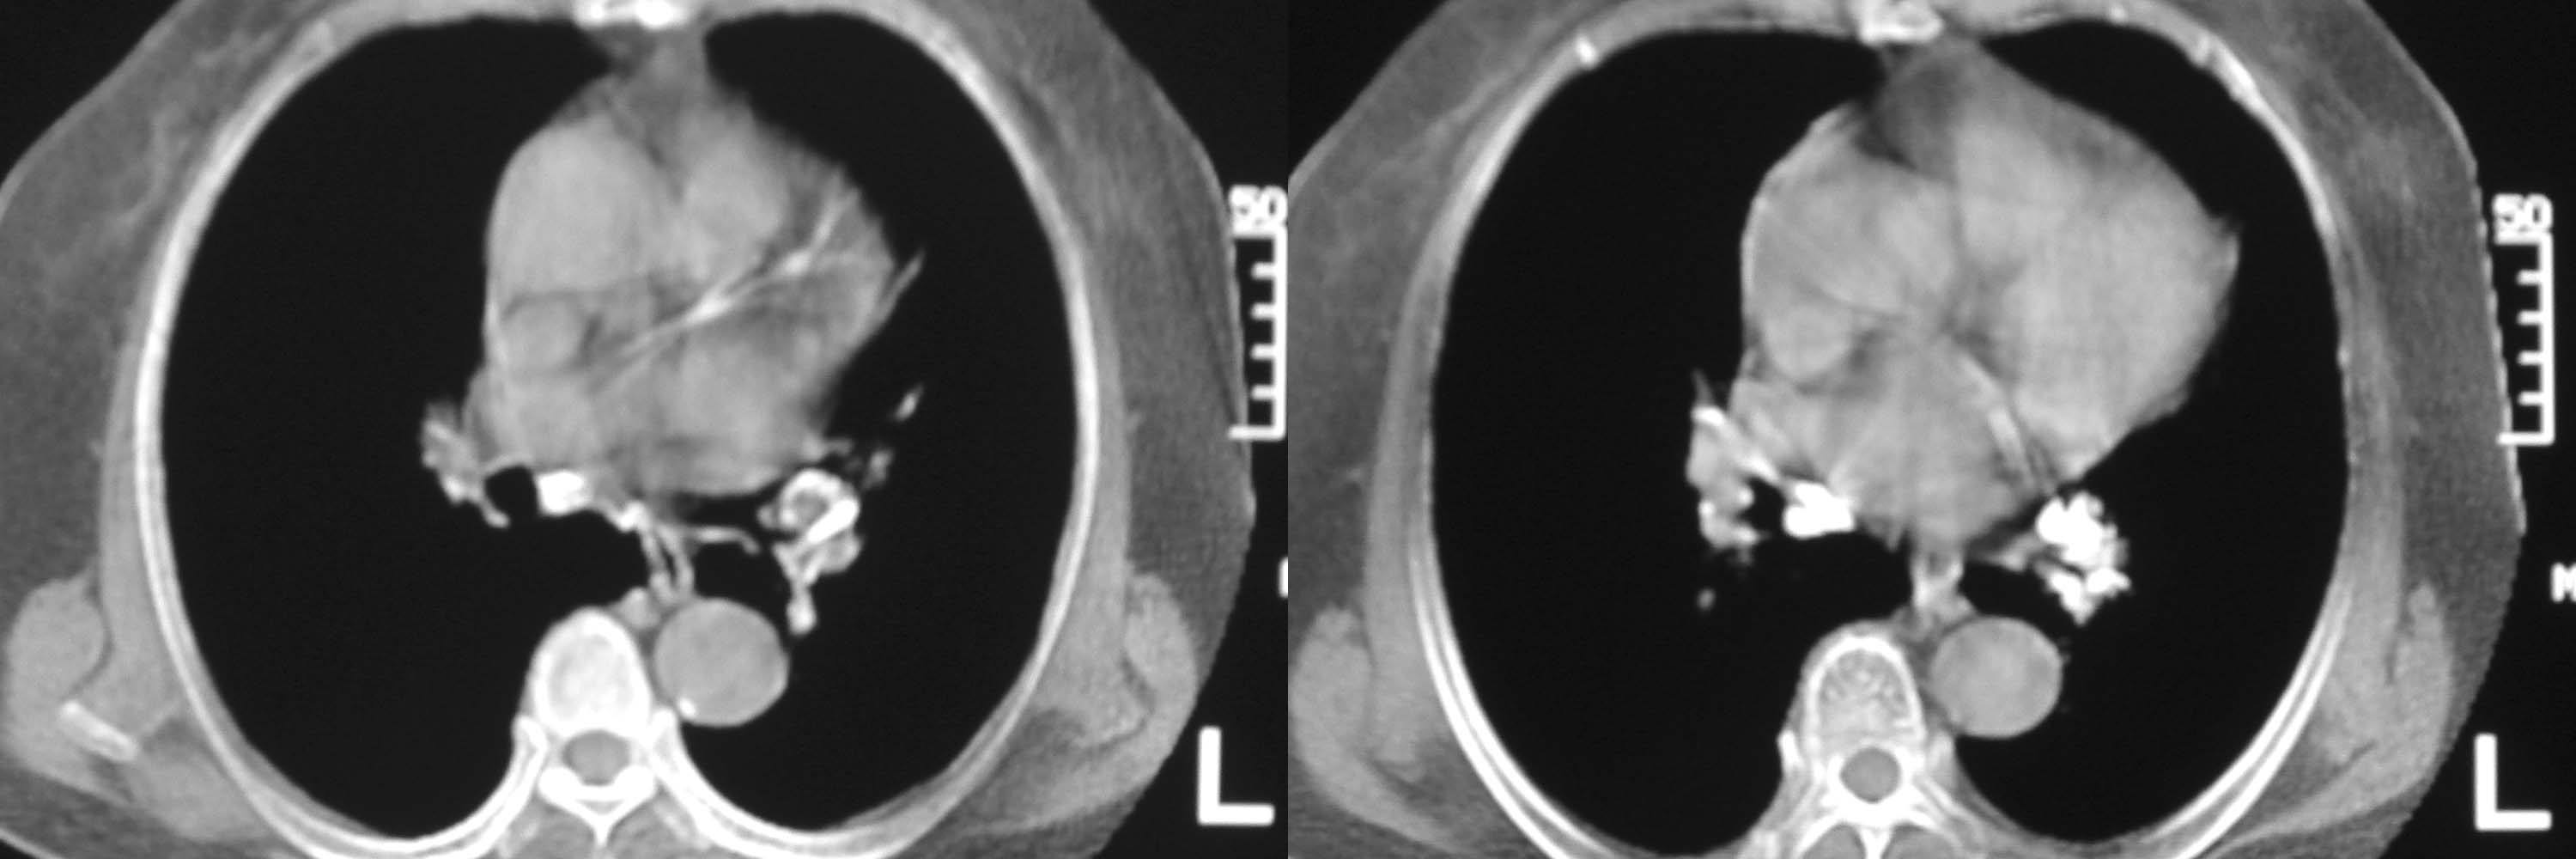

女78岁咳嗽咳痰无咳血平片报右上肺不张、慢支、肺气肿、请老师们帮忙看看,箭头所指是什么?是占位吗?有肺气肿吗?谢谢

箭头所指----多考虑-----右头臂静脉旁淋巴结钙化

可能是逾曲的头臂血管

可能是纡曲的头臂血管——支持。

箭头所指考虑血管影

箭头所指考虑血管影;纵隔内及双肺门区多发淋巴结钙化;不支持肺气肿。

箭头所指考虑血管影(头臂血管);纵隔内及双肺门区多发淋巴结钙化;不支持肺气肿。